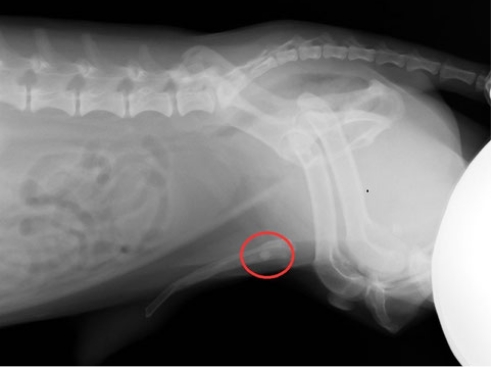

尿路(膀胱・尿道)結石

尿路結石は犬・猫の泌尿器疾患の中では比較的よく診察する疾患です。

尿路結石が形成される要因は、オシッコの中の塩類濃度が高い、塩類が結晶化されやすい尿pH、オシッコが膀胱内に長い時間溜まっている(オシッコを我慢している)、細菌感染を起こしている、などが考えられます。

結石に伴う症状とは?

膀胱炎症状を出します。頻尿・血尿が主な症状です。男の子の場合、膀胱から結石が出て尿道で詰まってしまい排尿障害(何度もオシッコをする体勢をするがオシッコが出ない)を起こすケースもあります。

診断は尿検査をはじめレントゲン検査・超音波検査を行い結石の有無・個数また膀胱の状態を診ていきます。

治療は結石の種類・症状・結石の大きさなどによって異なります。

食事療法によて改善するケースもありますが、外科手術によって結石の摘出を行うケースが多いと思います。

実際の症例

16歳8ヶ月のミニチュアダックスフンドです。

排尿困難とのことで来院されました。以前より膀胱結石の存在は知っていたとのことですが、主だった症状もなく高齢とのこともあり食餌療法で経過を追っていたとのことでした。当院でのレントゲン検査ではペニス内に結石が詰まっている所見が認められました。(犬のペニスには陰茎骨という骨があります)赤丸で示した部位で、陰茎骨内に丸い結石がありこれが排尿を妨げていました。

カテーテルで結石を膀胱内に押し戻し排尿ルートを確保し後に結石摘出手術を行いました。

• ミニチュアダックスフンド

• レントゲン検査

• 膀胱結石

今回の症例はかなり高齢な犬です。しかし結石が詰まると『苦しそうにしている姿が辛い』と飼い主様も手術を希望されました。 全身麻酔は、複数の鎮痛薬・鎮静薬を使い麻酔薬量を減らすことができる‘コンビネーション麻酔’を行い、心拍・血圧などを持ち上げ安定させる薬を使いながら麻酔を行い手術をしました。開腹後、膀胱を切開し結石を摘出した後、膀胱の洗浄を行い切開した膀胱を縫合し閉腹という術式です。術後の入院中は排尿もスムーズで食欲もあり状態の安定を確認したのち退院としました。 現在は抜糸を終え飼い主さまと食餌などを相談しながら経過を診ています。